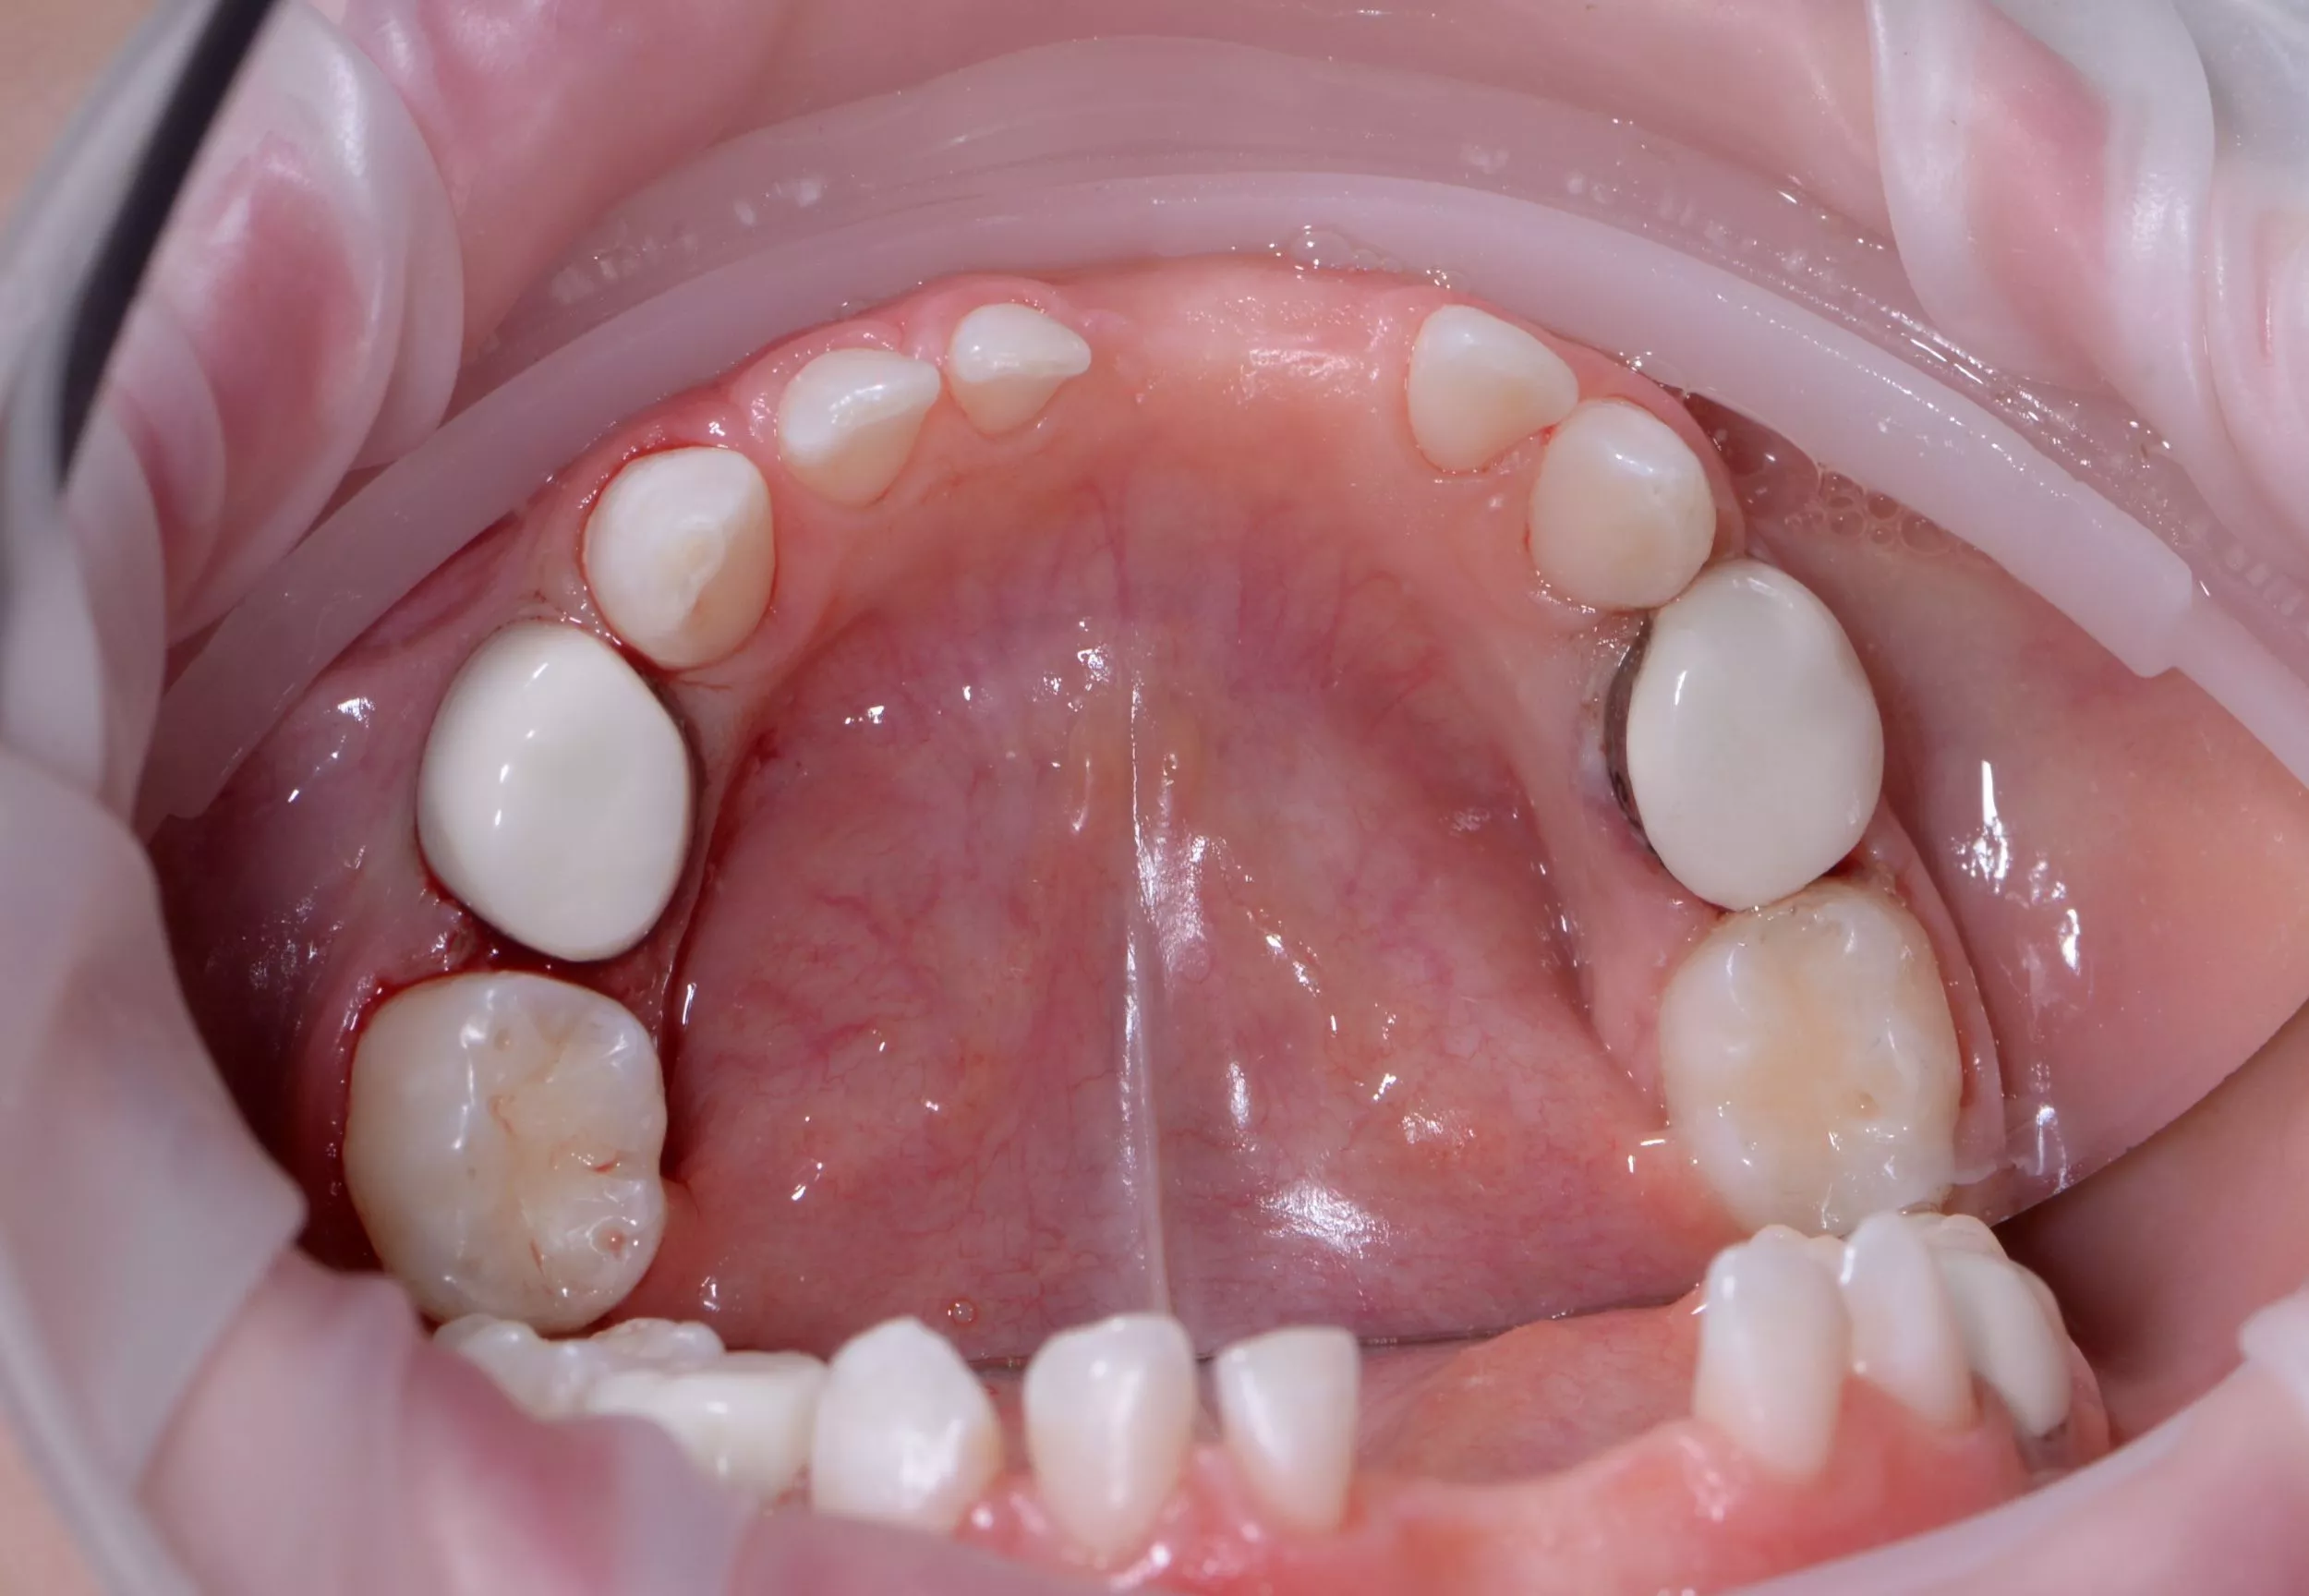

До